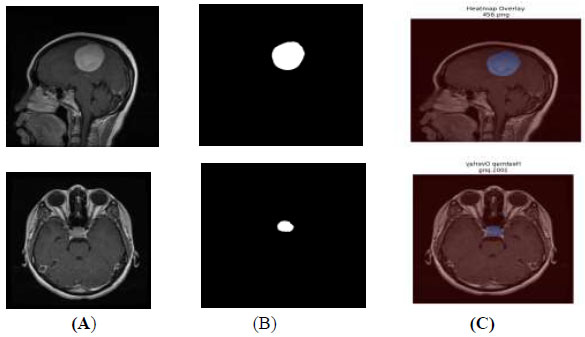

The segmented output mask is a plain black-and-white image and is separate from the original MRI scan, making it difficult to visualize the actual tumour area on the MRI. A heatmap overlay, which adds color to the tumour region, can be blended on top of the original MRI image, as shown in Fig. (11). This heatmap overlay helps non-technical AI users, such as doctors, quickly identify the predicted tumour region within the original MRI scans.

Heatmap overlay (A) original image (B) segmented output (C) heatmap overlay.